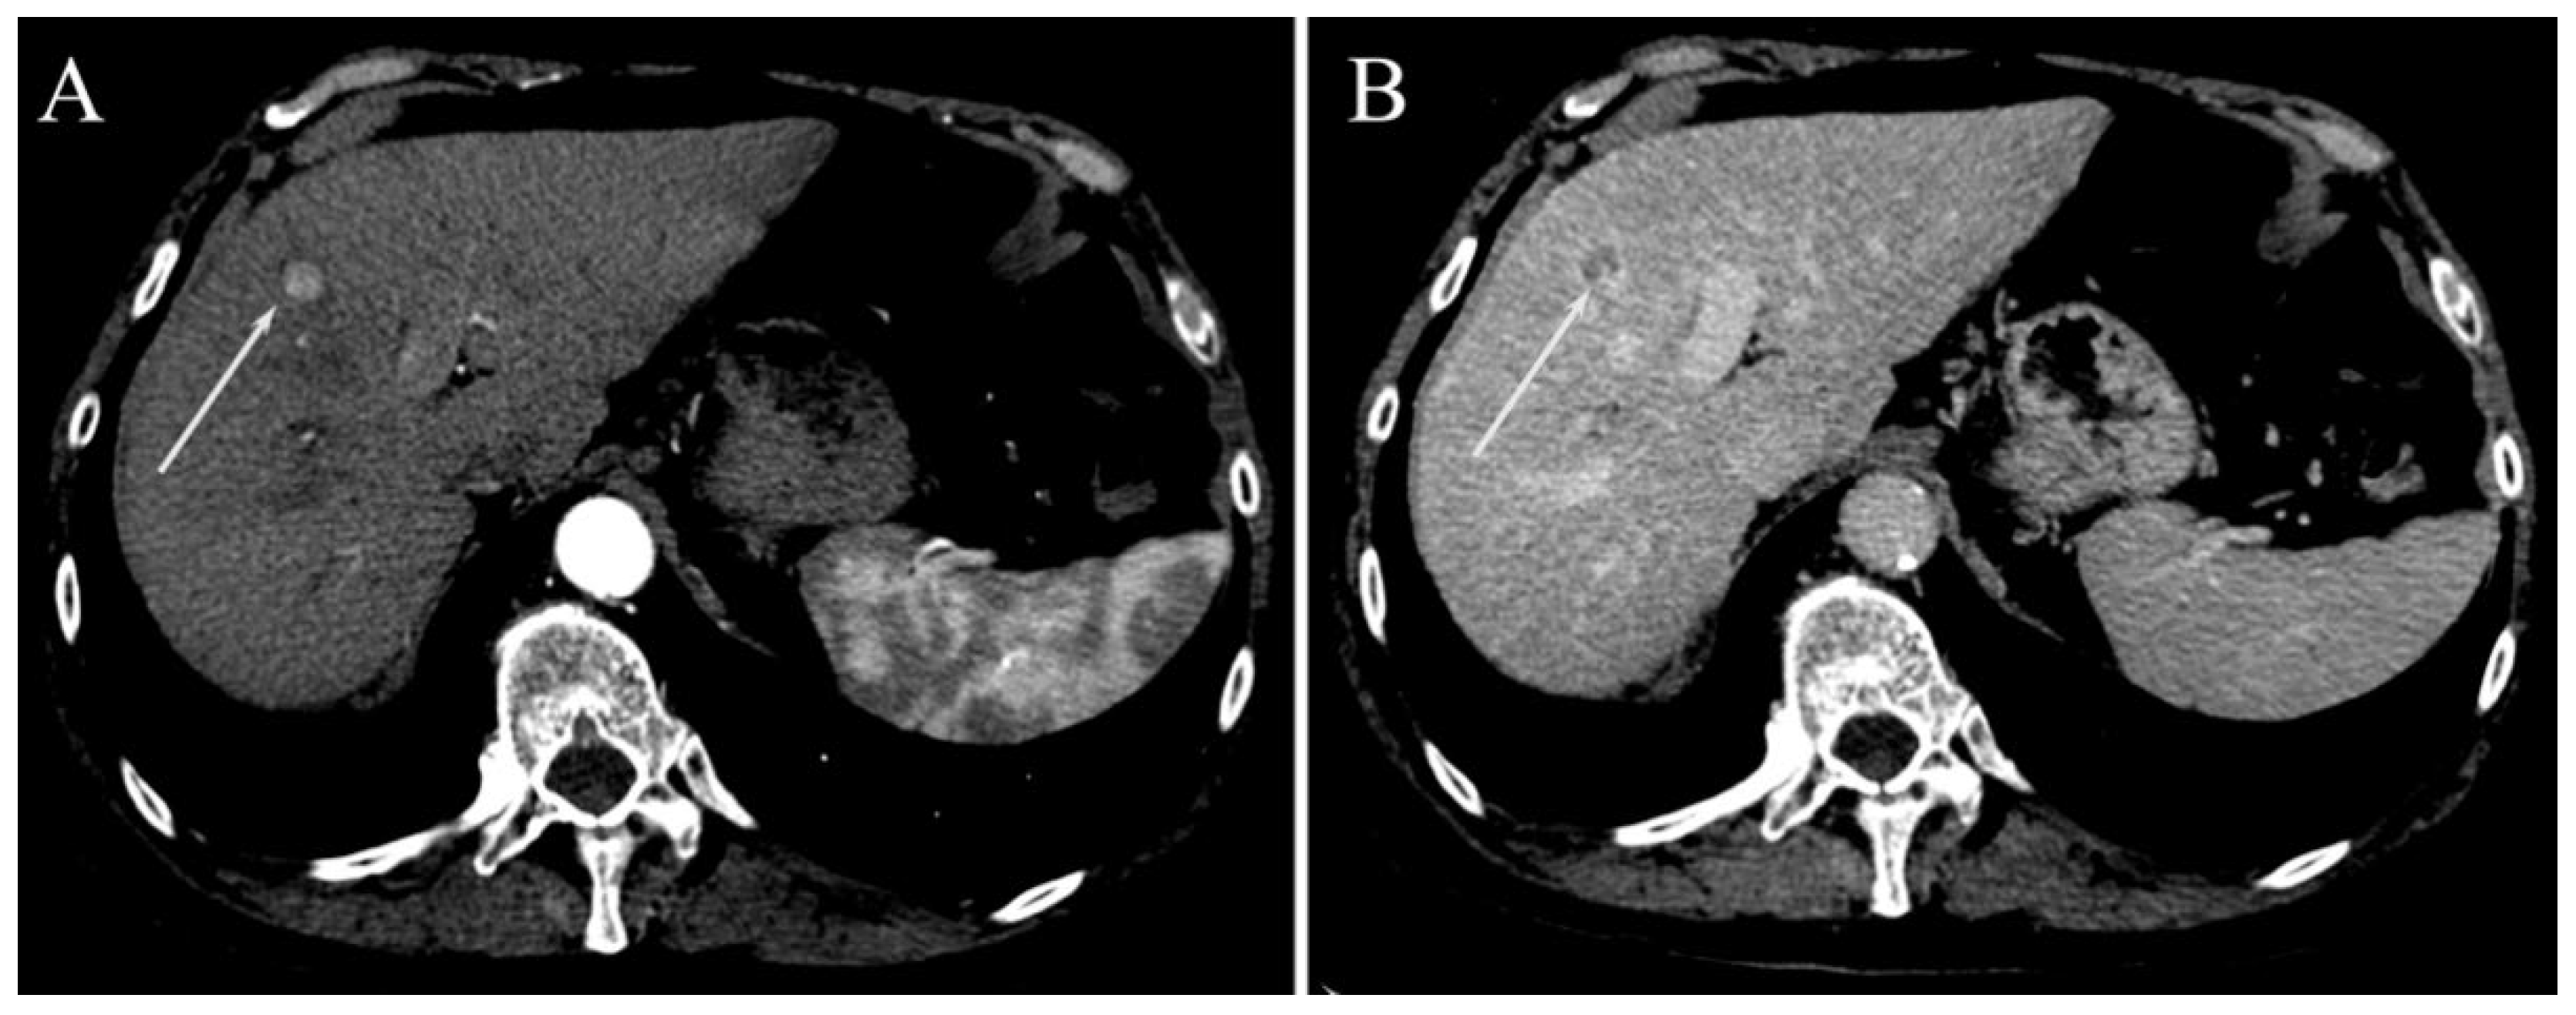

| Irregular margins | 21 (58.3%) | 26 (47.3%) | 0.391 |

| TTPVI | 14 (38.9%) | 11 (20%) | 0.058 |

| Peritumoral enhancement | 4 (11.1%) | 6 (10.9%) | 1.000 |